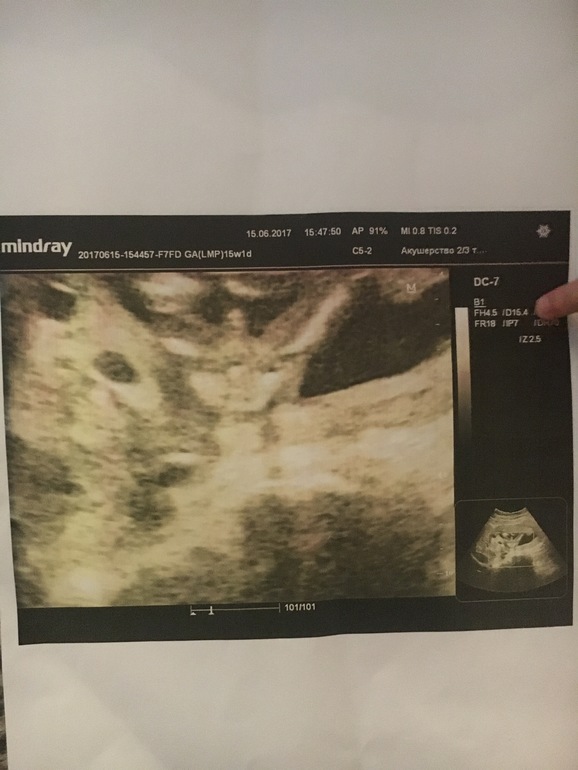

Пол малышаФото с узи в 15 недель..врач конечно сказал что эту морковку сложно не заметить и это мальчик) на узи в 17 недель (по показаниям) малыш сидел на попе,но долго смотрели и в итоге узист(другой) сказал что мальчика не видит..так что это тогда на фото с 15 недель?? Пуповина такая может быть?

Писюн с пуповиной легко спутать, если смотреть на малыша сбоку, а в таком положении и на таком сроке, мне кажется, уже маловероятно.

ну пуповина пульсирует и врач узи не смогла бы спутать такой кусок пуповины с писюном) Дождитесь 2 узи)

Вот фото моего мальчика, ваш тоже на мальчика похож